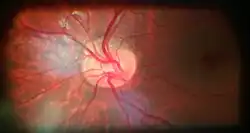

![]() Ophthalmoscopy photograph showing the optic disc as a bright area on the right where blood vessels converge. | |

The optic disc or optic nerve head is the point of exit for ganglion cell axons leaving the eye. Because there are no rods or cones overlying the optic disc, it corresponds to a small blind spot in each eye.

The ganglion cell axons form the optic nerve after they leave the eye. The optic disc represents the beginning of the optic nerve and is the point where the axons of retinal ganglion cells come together. The optic disc in a normal human eye carries 1–1.2 million afferent nerve fibers from the eye toward the brain. The optic disc is also the entry point for the major arteries that supply the retina with blood, and the exit point for the veins from the retina.[1]

The optic disc is located 3 to 4 mm to the nasal side of the fovea. It is a vertical oval, with average dimensions of 1.76mm horizontally by 1.92mm vertically.[2] There is a central depression, of variable size, called the optic cup. This depression can be a variety of shapes from a shallow indentation to a bean pot—this shape can be significant for diagnosis of some retinal diseases.